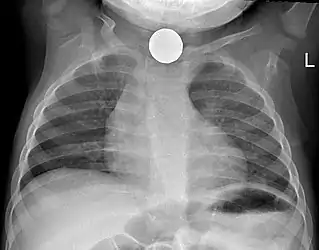

Radiography is the most common form of imaging used in the initial assessment of a foreign body presentation. Most patients receive a chest x-ray to determine the location of the foreign body.[2] Lateral neck, chest, and bilateral decubitus end-expiratory chest x-rays should be obtained in patients suspected of having aspirated a foreign body.[6] However, the presence of normal findings on chest radiography should not rule out foreign body aspiration as not all objects can be visualized.[2] In fact, up to 50% of cases can have normal findings on radiography.[7] This is because visibility of an object depends on many factors, such as the object's material, size, anatomic location and surrounding structures, as well as the patient's body habitus.[13] X-ray beams only show an object if that object's composition blocks the rays from traveling through, making it radiopaque and appearing lighter or white on the image. This also requires it to not be stuck behind something that blocks the beams first.[13] Objects that are radiopaque include items made of most metals except aluminum, bones except most fish bones, and glass. If the material does not block the x-ray beams it is considered radiolucent and will appear dark which prevents visualization.[13] This includes material such as most plastics, most fish bones, wood, and most aluminum objects.[13]

Signs on x-ray that are more commonly seen than the object itself and can be indicative of foreign body aspiration include visualization of the foreign body or hyperinflation of the affected lung.[13] Other x-ray findings that can be seen with foreign body aspiration include obstructive emphysema, atelectasis, and consolidation.[8]